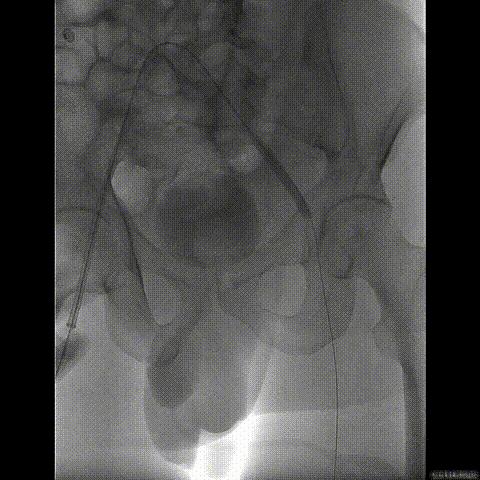

经瓣架网眼挂上指引管

反复确认指引管经瓣架网眼

指引管经瓣架网眼

经网眼置入导丝

置入4.0mm*23mm微创冠脉支架

定位并释放支架

退出球囊扩张突入瓣架部位

复查冠脉造影

多体位复查冠脉造影